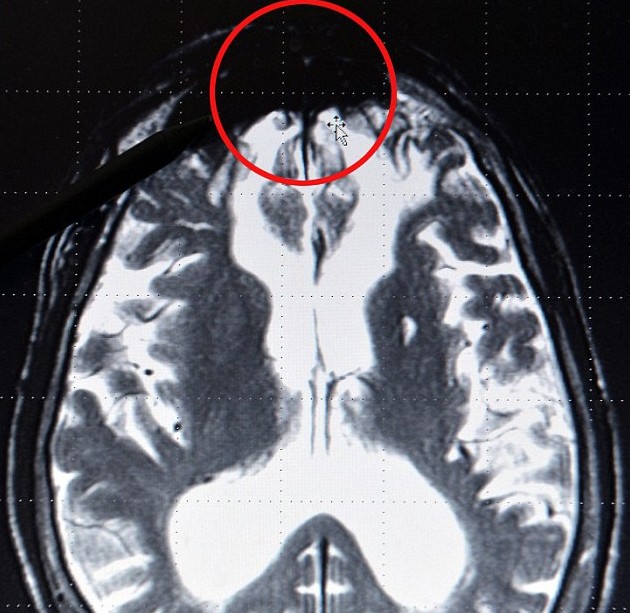

德國專家揭秘罪犯大腦結構:邪惡黑影潛伏特定區域

“邪惡片區”位于大腦前端。

通過觀察年輕人的大腦X光片,羅特博士推測出前額處大腦機能潛在失調的人,將有66%的可能性實施暴力犯罪。根據他的理論,沒有兩個暴力罪犯是相同的,但他們主要可以分為三大類:第一種是心理健康但受到環境影響而從事打、偷、搶等犯罪活動;第二種是精神受過刺激的人,他們對周圍世界懷有敵意和脅迫感;第三種是純粹的精神變態,就像希特勒那樣的極端分子。

羅特博士特意指出,不是所有的暴力罪犯都是天生的,有很多是受不良環境的影響而走上了不歸路。“其實一些人從幼兒園開始其大腦就出現異常,社會應該在他們成為罪犯前,就給予他們及其家庭支持和援助。”